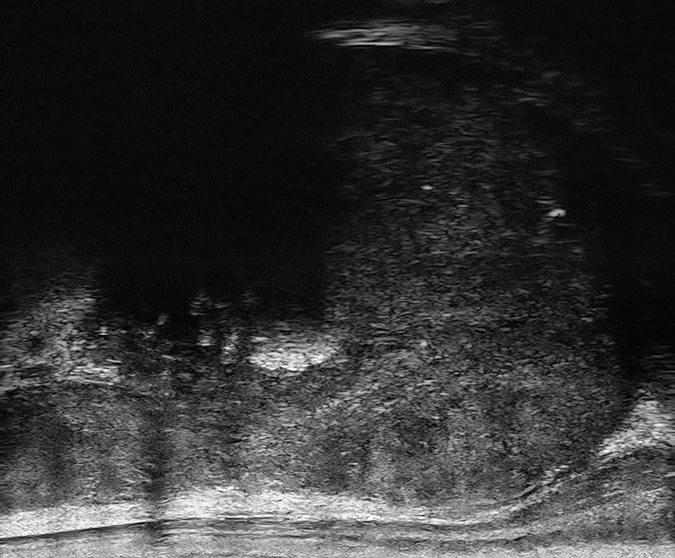

PRI-MUS 5

Irregular Shadowing or Mixed-echo lesions or Irregular Prostate/PZ border